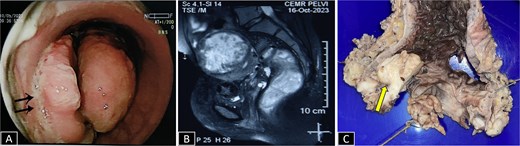

A 37-year-old female presented with a 2-year history of non-cyclical, recurrent rectal bleeding, significant weight loss, altered bowel habits, and spontaneous passage of polypoid tissue per rectum. Advanced imaging modalities, including computed tomography scan and contrast-enhanced MRI, demonstrated an aggressive local disease pattern with transmural rectal wall thickening, mesorectal fat stranding, and loss of intervening fat planes, features favoring a malignant lesion (Fig. 1A and B). Despite extensive diagnostic workup, including multiple biopsies, findings remained inconclusive, limited to nonspecific granulation tissue, inflammatory changes, and hyperplastic or adenomatous polyps with low-grade dysplasia. Pelvic imaging also revealed uterine fibroids and adnexal abnormalities. Ongoing diagnostic uncertainty necessitated a lower anterior resection with diversion loop ileostomy, which was complicated by persistent postoperative purulent discharge and poor clinical recovery, Gross examination of the resected rectal segment showed a diffusely thickened wall with multiple mucosal ulcerations and a well-circumscribed polypoid lesion measuring 3 cm in maximum dimension (Fig. 1C). Histological evaluation revealed ulceration with granulation tissue, along with multiple foci of ectopic endometrial glands and stroma within the submucosa and muscularis propria. Immunohistochemistry (IHC) confirmed the endometrial origin, with strong estrogen receptor (ER) positivity in both the glands and stromal component (Fig. 2). These findings confirmed the rare diagnosis of polypoidal rectal endometriosis, illustrating the protean clinical and pathological manifestations of the disease and its potential to mimic malignancy, leading to significant diagnostic delay.

(A) Sigmoidoscopy showing a polypoidal growth with surface ulceration (arrow) in the rectum involving more than 2/3 of the circumference. (B) CE MRI pelvis in a T2-weighted sequence reveals a heterogeneously enhanced hyperintense lesion with transmural involvement reaching up to the muscularis propria. (C) Gross specimen of proctosigmoidectomy showing a pedunculated polyp with petechial hemorrhages (arrow).